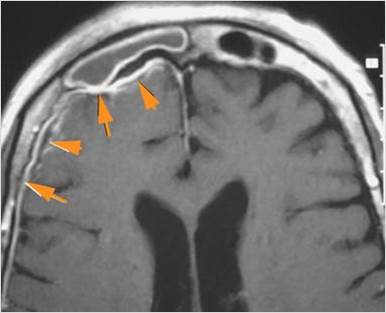

There is a subperiosteal fluid collection or abscess along the boney walls of the anterior or middle cranial fossa. |

Yes | NA |

There is an epidural fluid collection or abscess along the boney walls of the anterior or middle cranial fossa. |

There is brain edema specifically involving the frontal and temporal lobes. |

There is cerebritis specifically involving the frontal and temporal lobes. |

Findings are consistent with the clinical diagnosis of acute or subacute sinusitis superimposed on chronic mucocele with intracranial complications of epidural empyema along the orbital roof and early frontal lobe cerebritis.